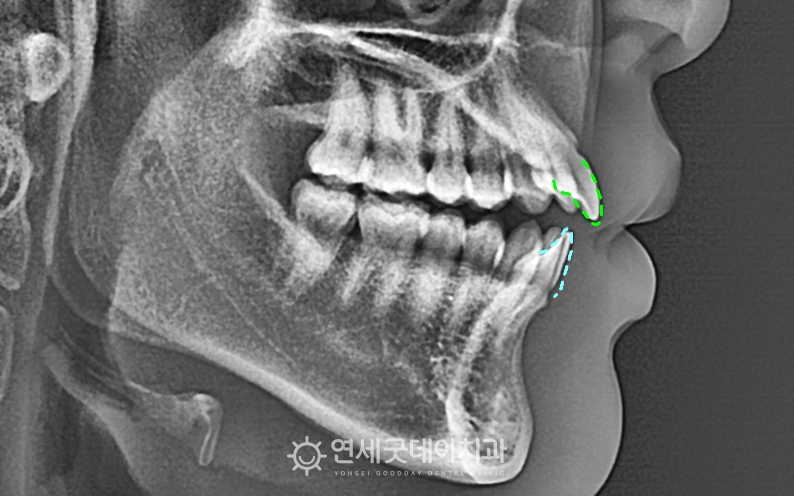

스플린트를 이용한 턱관절교정 후 교합이 일정해지고 환자분은 비발치로 진행되었으며 상하악의 구치부 함입을 ▲ 개방교합 교정 후 엑스레이 (촬영시기 : 2025년 7월) 1년 6개월 간의 인비절라인 교정이 종결되었습니다.

상하악의 공간이 줄어들며 개방교합이 완전히 해소되었고, 환자분은 심미적 목적 보다도 ▲ 개방교합 교정 전후비교 안타깝게도 개방교합은 재발 가능성이 높은 형태로 이에 연세굿데이에서는 개방교합 케이스에 한해 긴 치료 받으시느라 고생 많으셨습니다 :) |